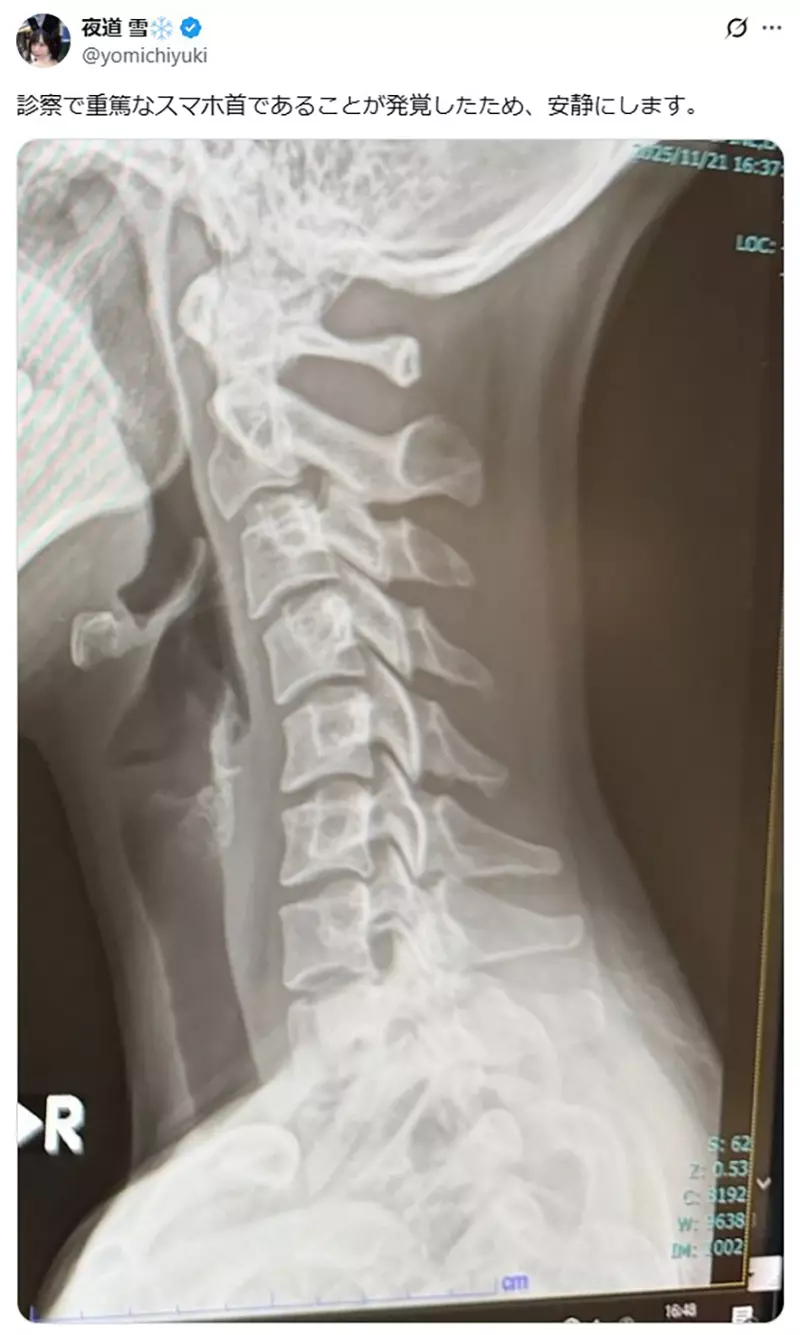

「檢查發現我的脖子有嚴重的低頭族症狀,所以我會好好休養。」

圖片來自:https://x.com/yomichiyuki/status/1991817077481758811